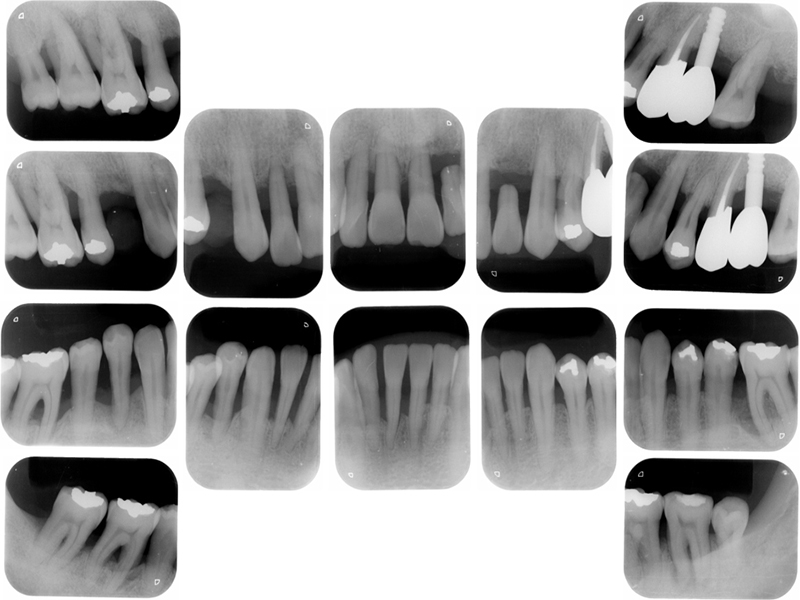

初診時X線写真